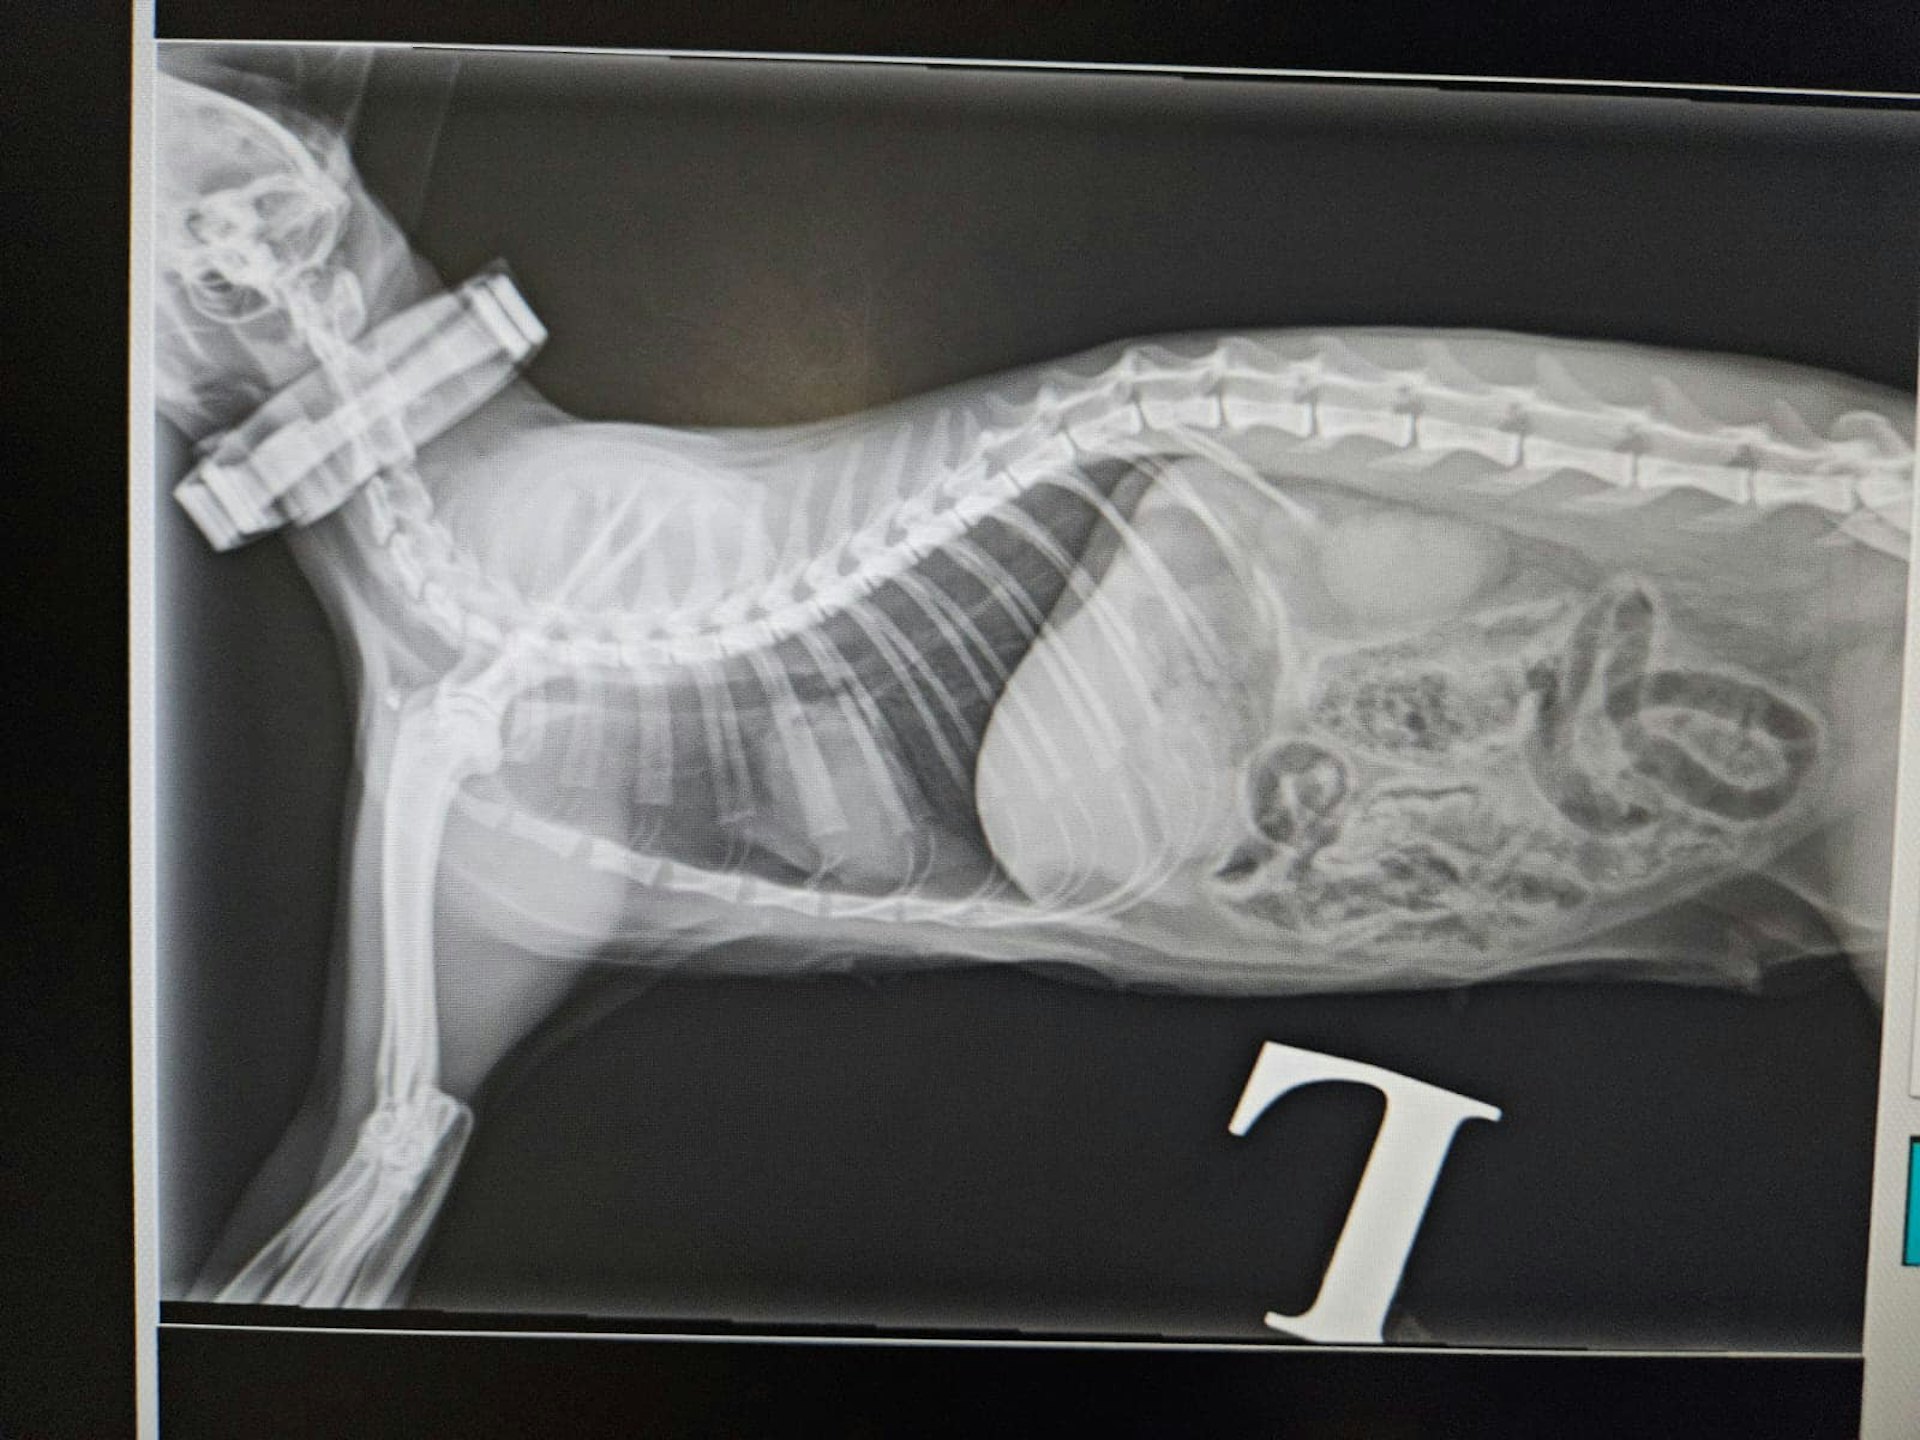

受傷貓隻接受X光檢查。(facebook專頁「毛守救援」圖片)